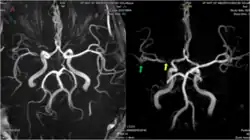

MRI and CT brain imaging is used to determine the severity of a stroke, and help guide treatment. Fluid attenuated inversion recovery (FLAIR) vascular hyperintensity (FVH) is a radiographic marker seen on brain imaging in acute ischaemic stroke. FVH can be used as a proxy for slow leptomeningeal collateral blood flow, and may help reveal which areas of brain tissue are potentially salvageable.[12]

Intracranial haemorrhage

A 2016 study compared patients awaiting carotid artery stenting for unilateral atherosclerotic plaques. Those with leptomeningeal collaterals evident on cranial angiography had a higher incidence of intracranial haemorrhage (ICH) after stenting. The authors argued that the presence of such collaterals on imaging should be considered a risk factor for ICH in patients where carotid stenting is otherwise indicated.[14]